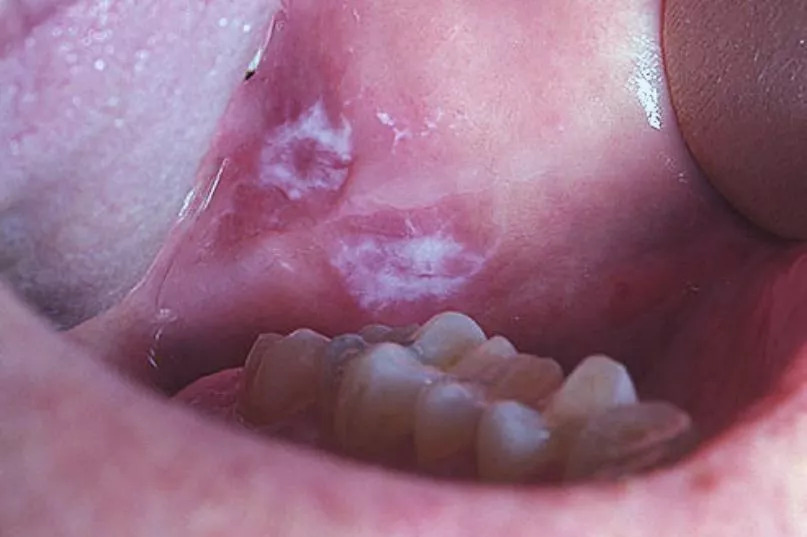

Trước khi phát triển thành vết nhiệt miệng rõ ràng, ung thư khoang miệng có thể bắt đầu bằng các tổn thương tiền ung thư (tiền ác tính) dưới dạng mảng màu bất thường, thường bị nhầm lẫn với nấm hoặc đổi màu niêm mạc.

Nhiệt miệng mà có 3 đặc điểm này e rằng "che giấu" tế bào ung thư, khám ngay còn kịp!- Ảnh 2.

Ảnh minh họa

Cụ thể là các mảng trắng (Leukoplakia) có màu trắng xám, dày, thường không gây đau, hoặc các mảng đỏ (Erythroplakia) có màu đỏ tươi, nhung. Nếu bạn nhận thấy bất kỳ mảng trắng hoặc mảng đỏ nào không thể cạo đi được và không biến mất trong vòng 2 tuần, cần phải đi kiểm tra ngay lập tức. Đây là dấu hiệu cảnh báo sớm nhất của sự phát triển tế bào ác tính.